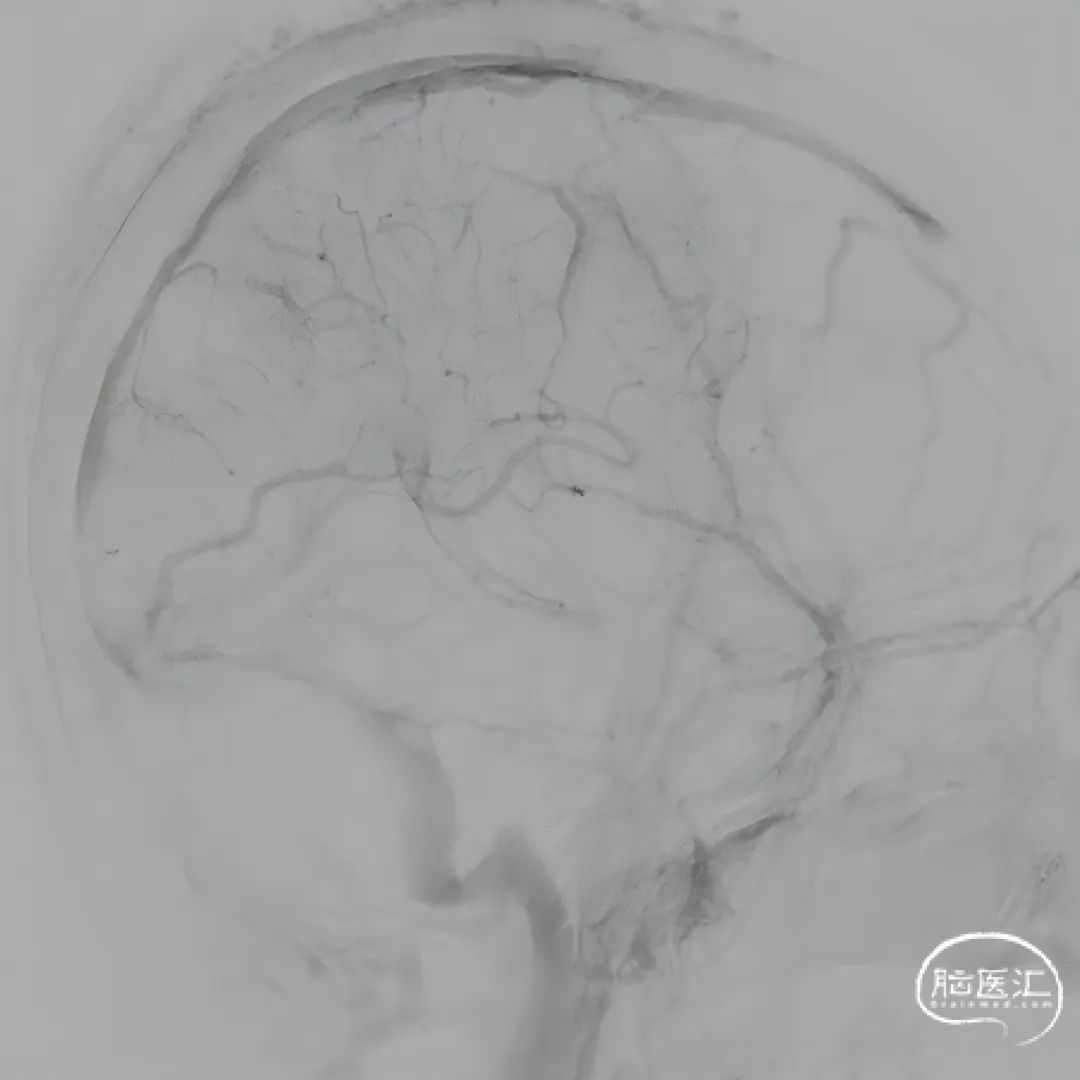

第二次术后次日复查头CT,置管溶栓3天后(4月6日)拔除微导管及静脉鞘,复查头颅MRV。